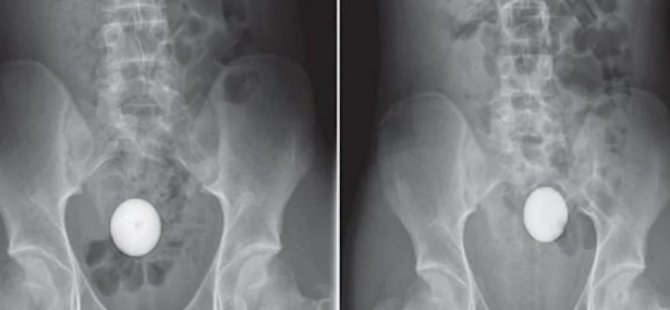

Avustralya'da 14 yaşında bir gencin anüsüne giren nesne, röntgen filmlerine bakıldığında pek anlaşılmıyor. İlk başta bunun bir yumurta olduğu sanılabilir ancak gencin vücuduna giren bu şey bir beyzbol topu.

Genç erkek çocuğu, beyzbol topunun anüsünden içeri kaçtığını ve geri çekemediğini fark edince büyük panik yaşayarak annesiyle beraber soluğu hastanede aldı. Çekilen röntgenlerde topun çocuğun bağırsaklarına yerleştiği görüldü.

İlaç yardımıyla topu çıkarmaya çalışan doktorlar bunu başaramayınca birçok yöntem denedi ancak hiçbiri sonuç vermedi. Topun bağırsaklarda ilerleyerek rektuma kadar gittiği görüldü.